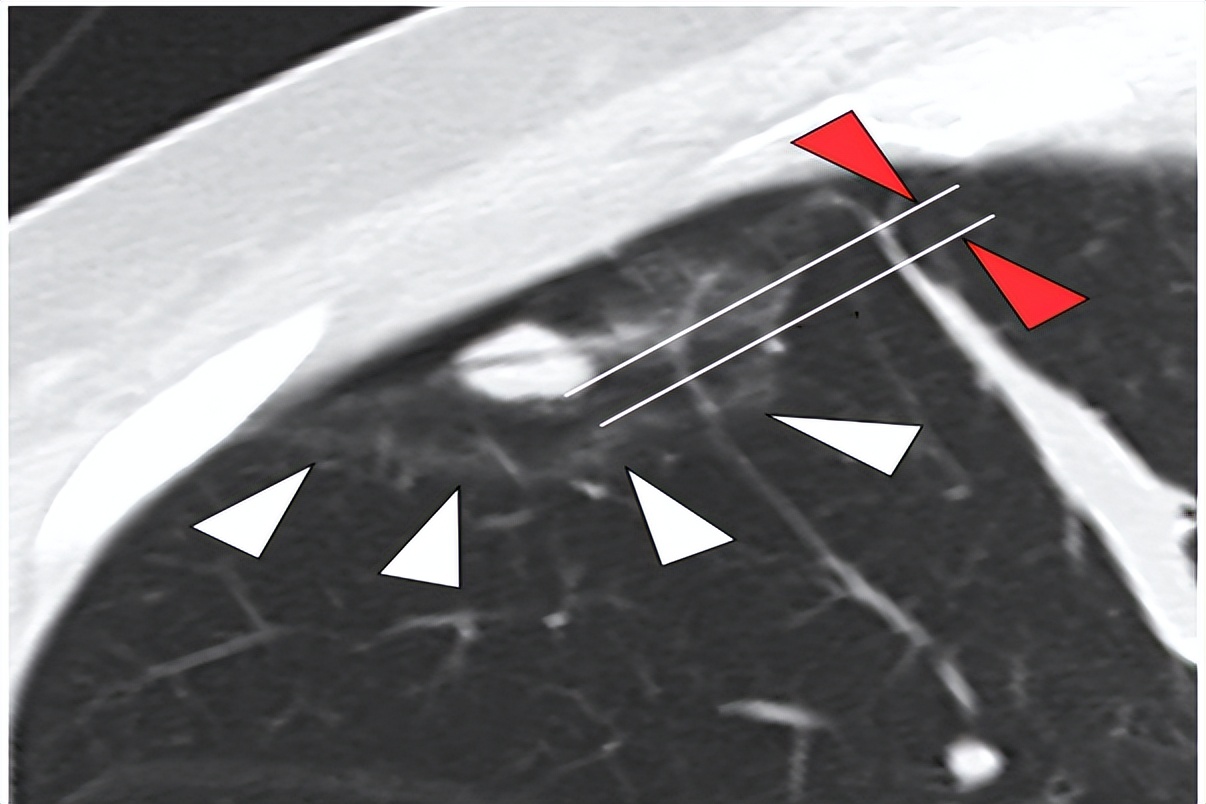

研究中,作者指出,针对射频消融患者,在消融后应该立即开展CT扫描以观察他们的消融有效范围。

因为消融治疗后往往会导致肺组织充血而形成CT上的磨玻璃表现。此时,若磨玻璃范围完整的包绕肺结节,可以认定消融完全;而若磨玻璃范围不能完整包绕肺结节,则认定消融不完全。

所谓消融边界距离,就是消融后的磨玻璃边界和肺结节边界之间的最小间距。